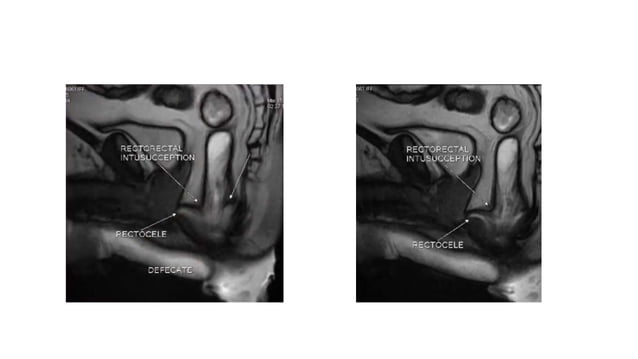

Defecographic characterization of functional abnormalities (absent ...